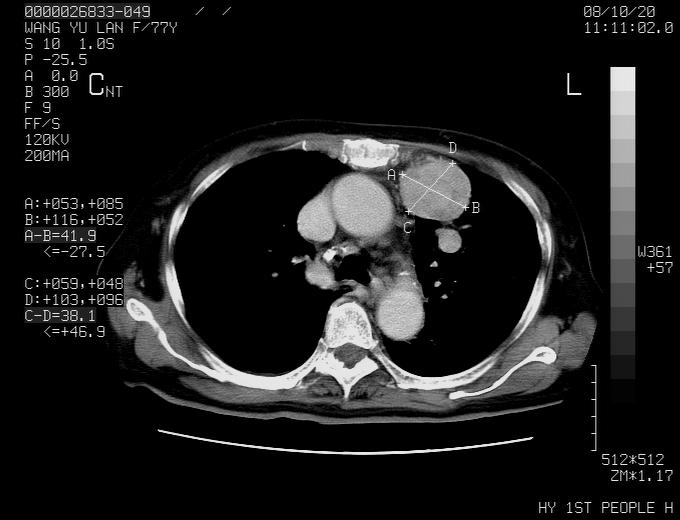

动脉期未见大血管同步强化,首先考虑周围型肺癌

动脉期病灶近中线侧可见星芒状与大血管同等强化密度,支持考虑血管畸形伴血栓形成,动脉期不曲型,不除外周围型肺癌

1、考虑avm可能性大。2、纵隔有肿大淋巴结,左肺上叶有炎性病变,不排除肺癌并转移可能。